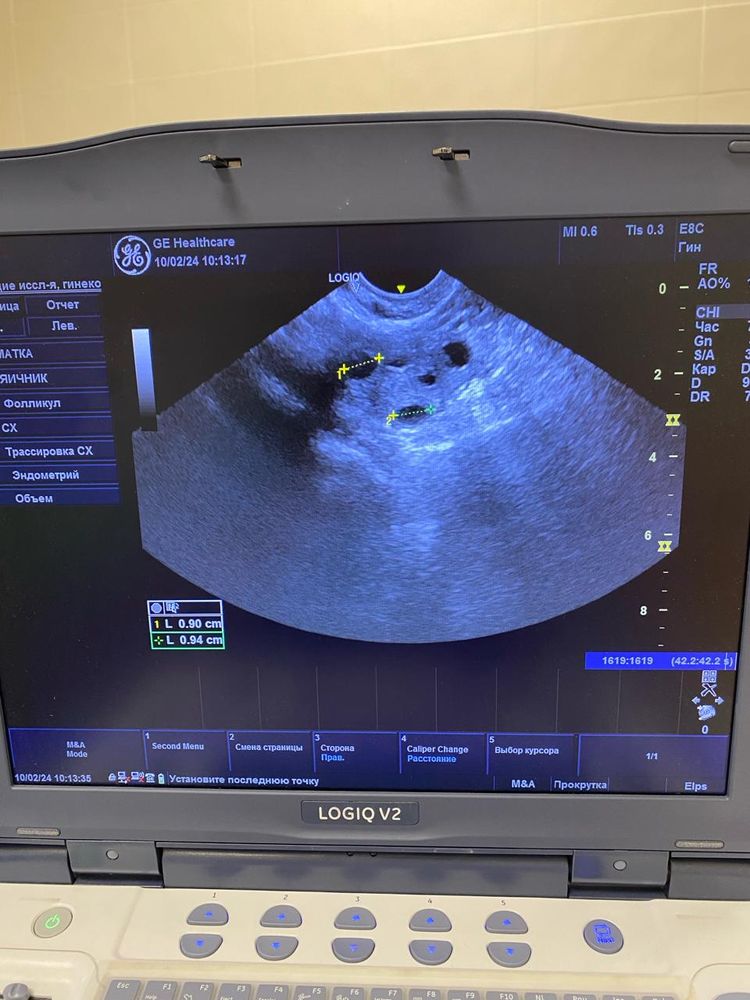

Вот вот овуляция это не понятно очень. Приложите протокол УЗИ

Ольга, по этим снимкам овуляция не вот вот. А до нее еще как минимум неделя от этого УЗИ. Фолликулы до 10 мм. И нет доминанта

Ольга, не нужны снимки, нужен протокол УзИ. Описание яичников, срез, ДФ, эндометрий. Врач узи в нескольких проекция смотрит. Я как врач, на этих снимках не вижу ДФ, фолликулы до 10 мм.. Поэтому вообще-то говорить что была овуляция сложно. Сейчас делать УЗИ нет смысла. Ждите менструацию, она начнется со дня на день. Делайте УЗи уже в след цикле в динамике, по мере роста ДФ и подтверждайте овуляцию через 7 дней после ее наступления и берите протоколы УЗИ. Сейчас мы с Вами просто гадаем на кофейной гуще.